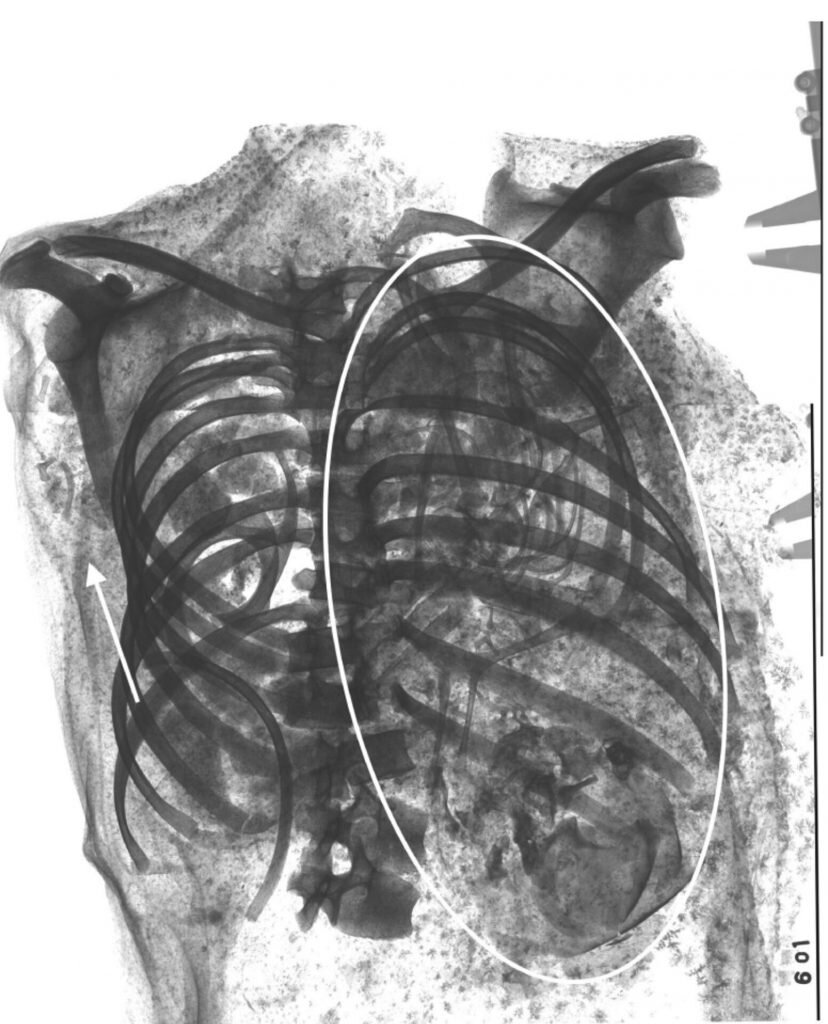

Останки второго плода в грудной клетке матери. Фотографии: Francine Margolis, David R. Hunt, International Journal of Ostearchaeology

Используя компьютерную томографию остеоархеологи повторно проанализировали необычную находку, чтобы разгадать детали этого кровавого инцидента. Вопреки исходным предположениям о странном кровавом ритуале сканирование показало наличие второго плода в грудной полости женщины. Более того в тазу матери ученые обнаружили оторванную голову второго младенца.

Таз мумии, в котором нашли оторванную голову. Фотографии: Francine Margolis, David R. Hunt, International Journal of Ostearchaeology

Исследователи полагают, что плод был обезглавлен во время родов — голова младенца застряла в родовых путях. О беременности двойней те, кто бальзамировал тело, по-видимому, не знали, а потому не удалили второй плод. Когда диафрагма мумии растворилась, нерожденный близнец мог переместиться из матки в грудную полость.